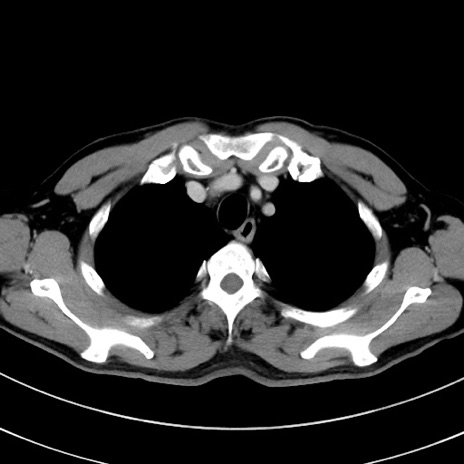

症例8(横断像)

【症例】 60歳代男性

【主訴】 黒色吐物

【現病歴】 4日前から嘔気自覚、2日前の朝食後にも嘔気あり、自分で手で嘔吐反射起こし嘔吐したところ血が混ざっていたため受診。

【既往歴】 5年前汎発性腹膜炎を伴う急性虫垂炎で手術、高血圧、前立腺肥大症、高脂血症

【身体所見】 腹部正中に手術癩痕あり 腹部平坦・軟圧痛なし膨満感あり

【データ】WBC 8400、CRP 4.54